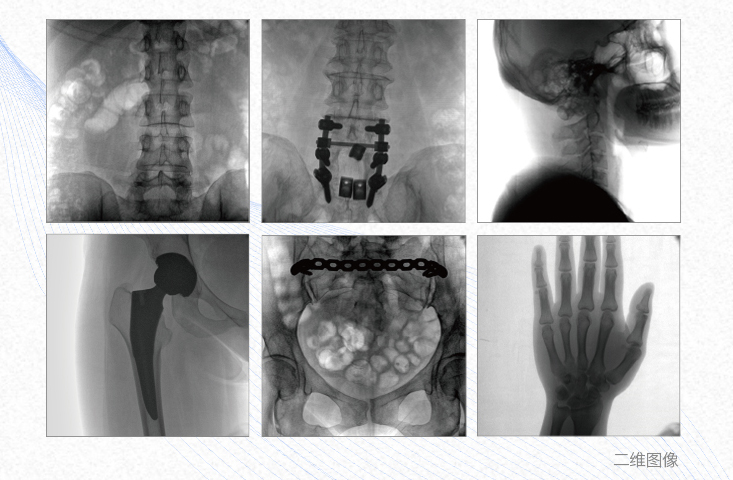

有效重建复杂的脊柱三维模型,提供准确的二维、三维图像,提高螺钉植入的准确性,缩短手术时间,减少并发症的概率,降低辐射的摄入。

例如骨盆骨折内固定术,可术中三维重建髋臼关节面,准确定位并植入螺钉,有效缩短螺钉植入的时间和透视暴露时间,减少术中及术后并发症发生的概率。

主要应用于肩关节、肘关节、髋关节、膝关节的关节置换及解剖复位的定位。它可以准确地置入假体,减少辐射时间,降低辐射剂量。

例如治疗先天性脊柱侧后凸畸形,可有效引导术者植入后路螺钉并切除半锥体,达到满意的截骨矫正效果。

术中三维成像和横断面图像提供多角度的手术诊断信息,辅助医生进行术中评估判断,诸如骨折复位情况和内植入螺钉的尺寸和位置,辅助手术更好地完成。

提供更大的术中三维成像视野,采集更多图像信息,可一次拍全全段颈椎、全段腰椎、七节胸椎、双侧骶髂关节、股骨头及单侧盆骨。